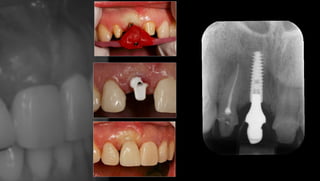

Eaed case 8